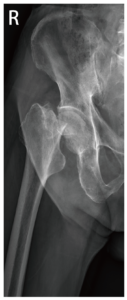

而股骨頸骨折又可分為「非移位的不完全性骨折」和「完全移位性骨折」,前者通常只需要內固定治療,後者則需要進行「雙極式半人工髖關節置換」手術治療,是因為股骨頸位在關節內,骨折後不易復原,且發生位移後會造成血管受傷,即便透過內固定把骨頭固定回去,缺乏血液供應的股骨頸仍會壞死,所以通常會藉由置換半套人工髖關節來治療。

手術前 手術後